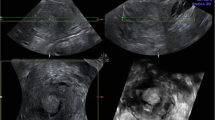

At TVUS, myometrial invasion appears as an iso- or hyperechoic tissue compared to the surrounding myometrium. An intact subendometrial halo (inner layer of myometrium) usually indicates no more than superficial invasion, whereas obliteration of the halo indicates deep invasion (Fig. 2). The cervix should be examined in a sagittal plane for tumor invasion into the cervical stroma [35]. The distance from the outer cervical os to the lower tumor margin is the only parameter that might have the potential to predict cervical invasion [14, 35].

66-year-old woman with post-menopausal bleeding. TVUS transverse image showing an endometrial mass with obliteration of subendometrial halo (arrows), reflecting myometrial invasion. Histopathology analysis confirmed the presence of a 5 cm endometrial adenocarcinoma invading 20 mm (> 50%) into the myometrium